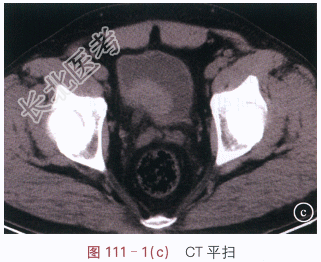

读片分析:图111-1(a)IVP示右侧肾脏功能受损,右侧肾盂、肾盏及输尿管未能显影;图111-1(b)IVP示膀胱内右侧壁类圆形充盈缺损,直径约4.5cm,边缘光滑;图111-1(c)CT平扫示膀胱右后壁见软组织肿块,大小约4.5cm×2.5cm,边缘较光整,周围膀胱壁增厚、僵硬,周围脂肪间隙清晰,右侧输尿管下端扩张;图111-1(d)CT增强示膀胱壁肿块明显强化,强化均匀。结合病史,患者诊断为膀胱癌。